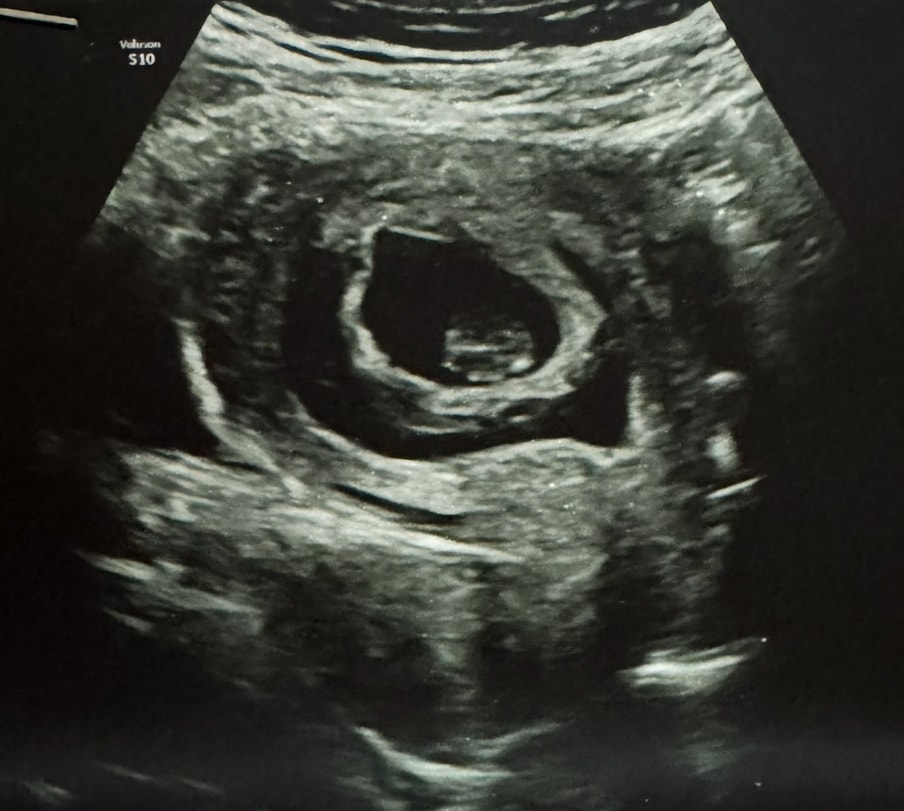

Ретрохориальная гематома 15 мм

Вот этот темный полукруг, это все была отслойка, и только сверху немного держалась малышка